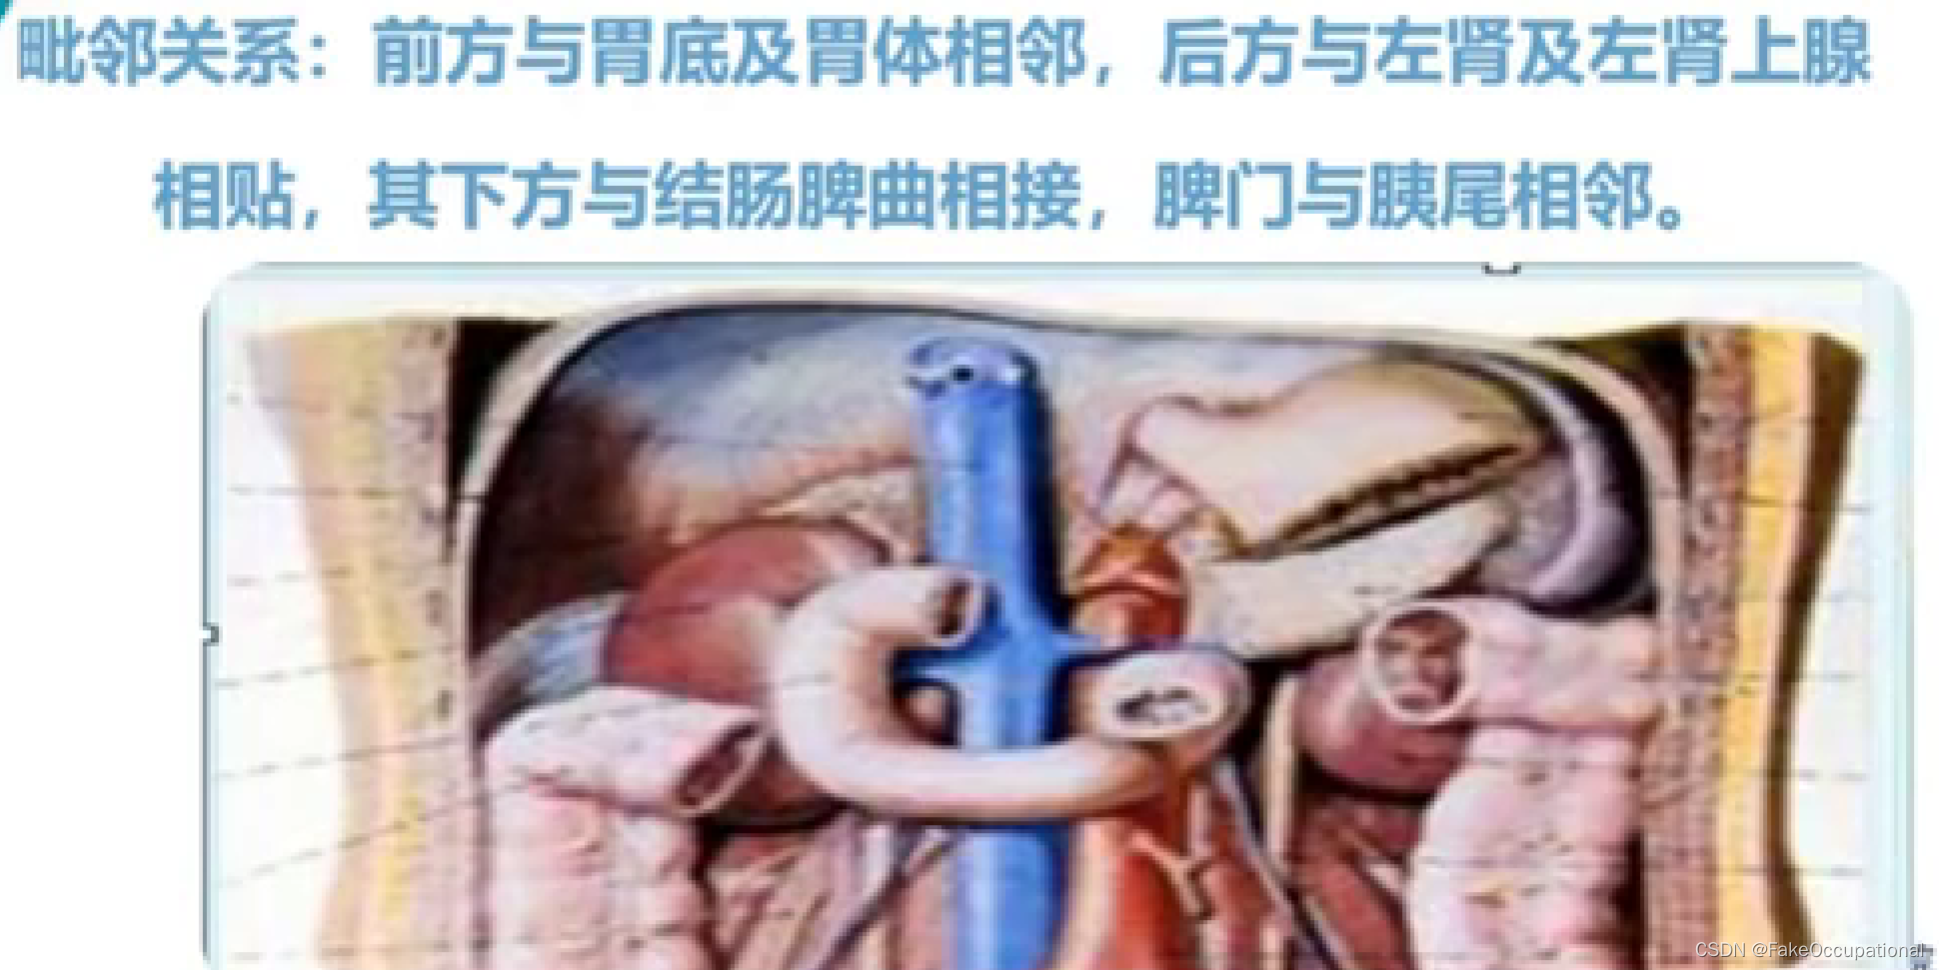

脾脏解剖及正常声像图